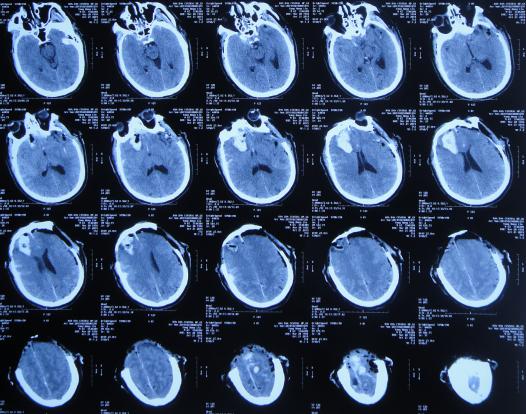

开颅术后第2天即2019年10月22日,仍昏迷,查头颅CT示积血未见减少( 图-3 ),给予腰椎穿刺术。

图-3: 2019年10月22日头颅CT

开颅术后第4天即2019年10月24日,查头颅CT示积血仍未明显减少( 图-4 )。

图-4: 2019年10月24日头颅CT